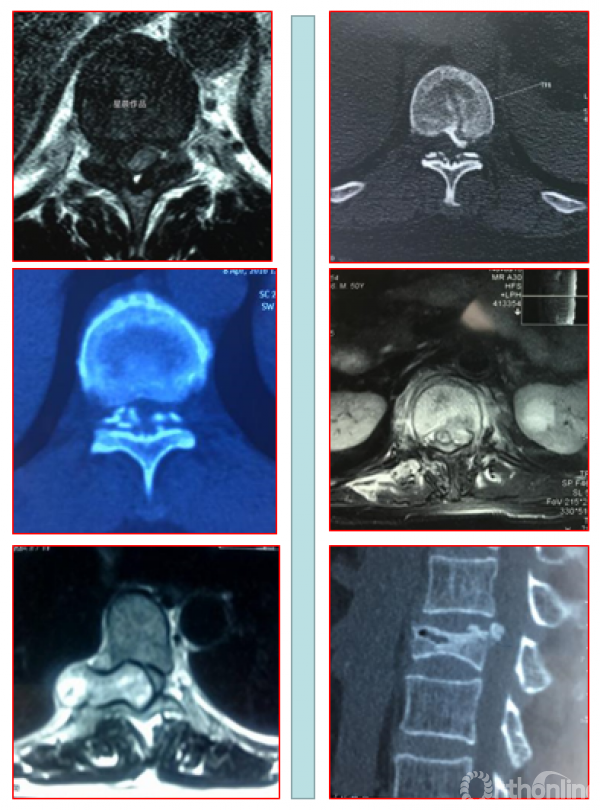

二、后纵韧带骨化形态学分型

1. 按照矢状位CT分为线型、鸟嘴型、连续波形、连续圆柱形和混合型。

OPLL的CT矢状位分型为A.线性(Linear type);B.鸟嘴型(Beak type);C.连续波形(Continuous waveform type);D.连续圆柱形(Continuous cylindrical type)。混合型(Mixed type)为同时具有A-D两种及以上类型